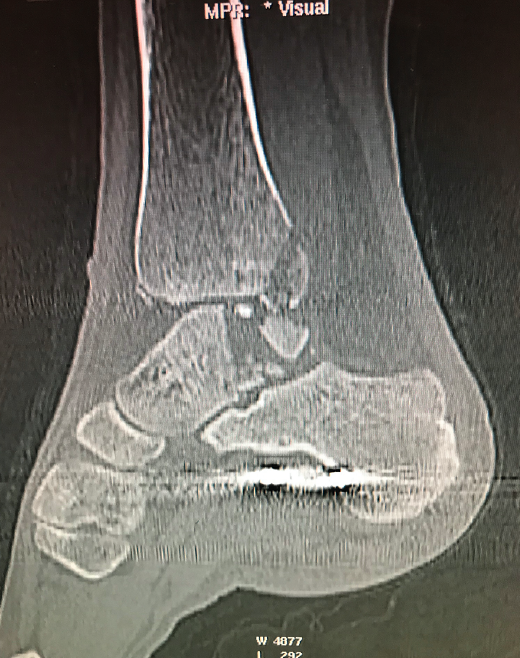

Figura 1. Fractura conminuta de la cúpula del astrágalo.

Se trata de un paciente varón de 35 años que, tras una precipitación, presenta impotencia funcional en el miembro inferior. Tras la valoración clínica y radiológica, se observa un estallido de la parte posterior de la cúpula astragalina (Figura 1).